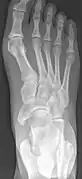

Type 2 on one foot (dark arrow) and type 3 on the other (white arrow)